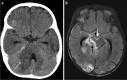

Tuberculosis (TB) remains one of the major public health threats worldwide, despite improved diagnostic and therapeutic methods. Tuberculosis is one of the main causes of infectious disease in the chest and is associated with substantial morbidity and mortality in paediatric populations, particularly in low- and middle-income countries. Due to the difficulty in obtaining microbiological confirmation of pulmonary TB in children, diagnosis often relies on a combination of clinical and radiological findings. The early diagnosis of central nervous system TB is challenging with presumptive diagnosis heavily reliant on imaging. Brain infection can present as a diffuse exudative basal leptomeningitis or as localised disease (tuberculoma, abscess, cerebritis). Spinal TB may present as radiculomyelitis, spinal tuberculoma or abscess or epidural phlegmon. Musculoskeletal manifestation accounts for 10% of extrapulmonary presentations but is easily overlooked with its insidious clinical course and non-specific imaging findings. Common musculoskeletal manifestations of TB include spondylitis, arthritis and osteomyelitis, while tenosynovitis and bursitis are less common. Abdominal TB presents with a triad of pain, fever and weight loss. Abdominal TB may occur in various forms, as tuberculous lymphadenopathy or peritoneal, gastrointestinal or visceral TB. Chest radiographs should be performed, as approximately 15% to 25% of children with abdominal TB have concomitant pulmonary infection. Urogenital TB is rare in children. This article will review the classic radiological findings in childhood TB in each of the major systems in order of clinical prevalence, namely chest, central nervous system, spine, musculoskeletal, abdomen and genitourinary system.